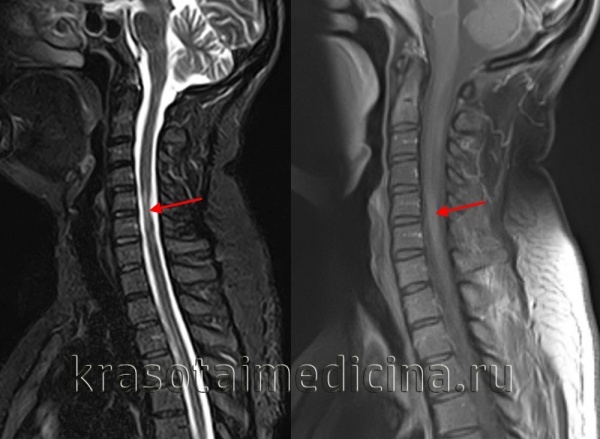

Демиелинизирующие заболевания мозга: МРТ изображения